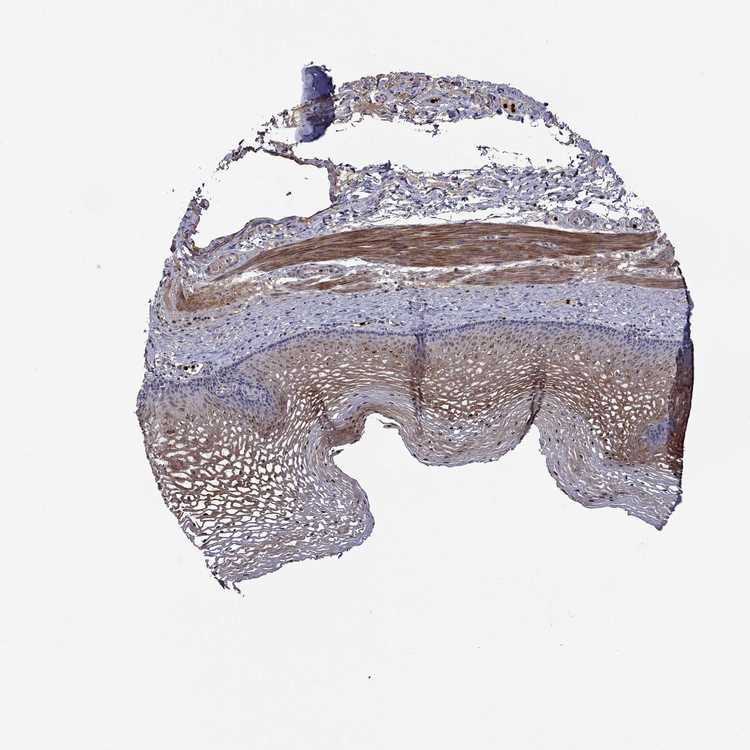

TISSUE PRIMARY DATA ESOPHAGUS Show tissue menu

ESOPHAGUS - Antibody stainingi

Antibody staining in the annotated cell types in the current human tissue is reported as not detected, low, medium, or high, based on conventional immunohistochemistry profiling in selected tissues. This score is based on the combination of the staining intensity and fraction of stained cells.

Each image is clickable and will lead to virtual microscopy that enables deeper exploration of all samples and also displays staining intensity scores, fraction scores and subcellular localization as well as patient and tissue information for each sample.

Antibody HPA051769Antibody HPA070534Antibody CAB056144

Squamous epithelial cells Not detectedHighNot detected